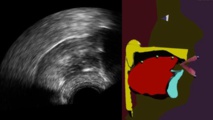

Imagen del nuevo sistema. A la izquierda, ecografía del sistema lingual, a la derecha, la reconstrucción virtual que permite observar en tiempo real los movimientos de la lengua y descubrir los defectos en la pronunciación. Imagen: CNRS

Investigadores franceses han desarrollado un sistema que permite visualizar, en tiempo real, los movimientos de nuestra lengua. Se trata de una ecografía lingual aumentada que, además de mostrar el rostro y los labios, hace aparecer la lengua, el paladar y los dientes, generalmente ocultos en el interior de la boca.

Desde hace años, investigadores anglosajones han desarrollado la técnica de la ecografía para la concepción de sistemas de retorno visual. En estos trabajos, la imagen de la lengua es obtenida colocando bajo la mandíbula una sonda similar a la que se utiliza para obtener la imagen de un feto. Esta imagen, sin embargo, es difícil de ser aprovechada por el paciente porque no es de buena calidad y también porque no da información alguna sobre el paladar o los dientes.

Desde hace años, investigadores anglosajones han desarrollado la técnica de la ecografía para la concepción de sistemas de retorno visual. En estos trabajos, la imagen de la lengua es obtenida colocando bajo la mandíbula una sonda similar a la que se utiliza para obtener la imagen de un feto. Esta imagen, sin embargo, es difícil de ser aprovechada por el paciente porque no es de buena calidad y también porque no da información alguna sobre el paladar o los dientes.